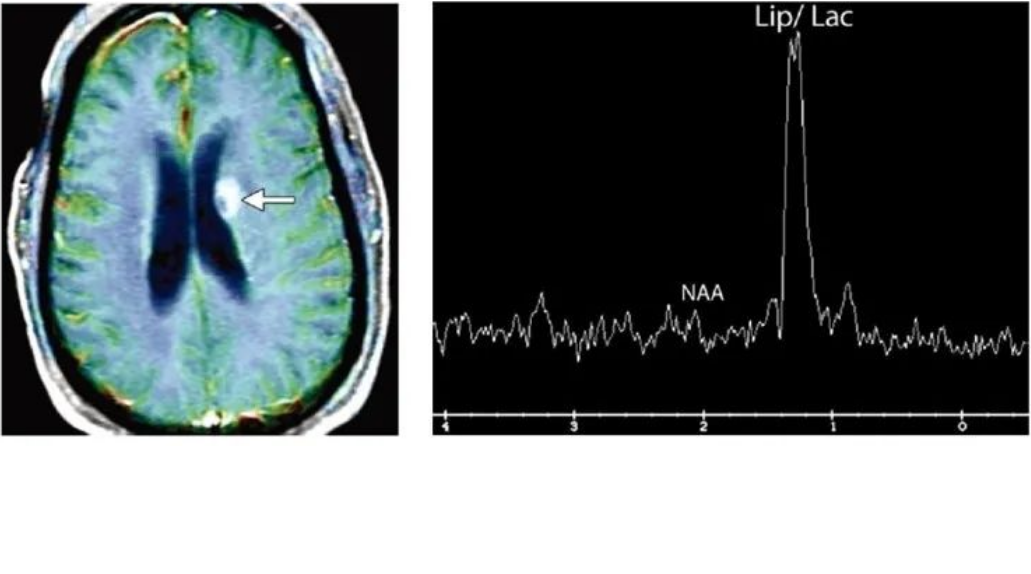

5.MRS磁共振波谱

放射性坏死:细胞崩解、坏死,NAA封及Cho封均下降,Lip升高。